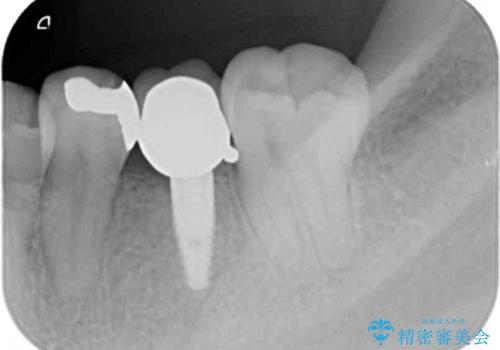

- 下の奥の銀歯を白くしたいとのことで来院されました。

セラミックインレーでの治療を行いました。

- 左下5 セラミックインレー 77,000円費用は治療当時の料金となります

銀の詰め物のやり替えは2回の来院で終わらせることができます。

下の歯は口を開けたときに外からよく見えるため、セラミックにやり替えることで印象が大きく変わります。